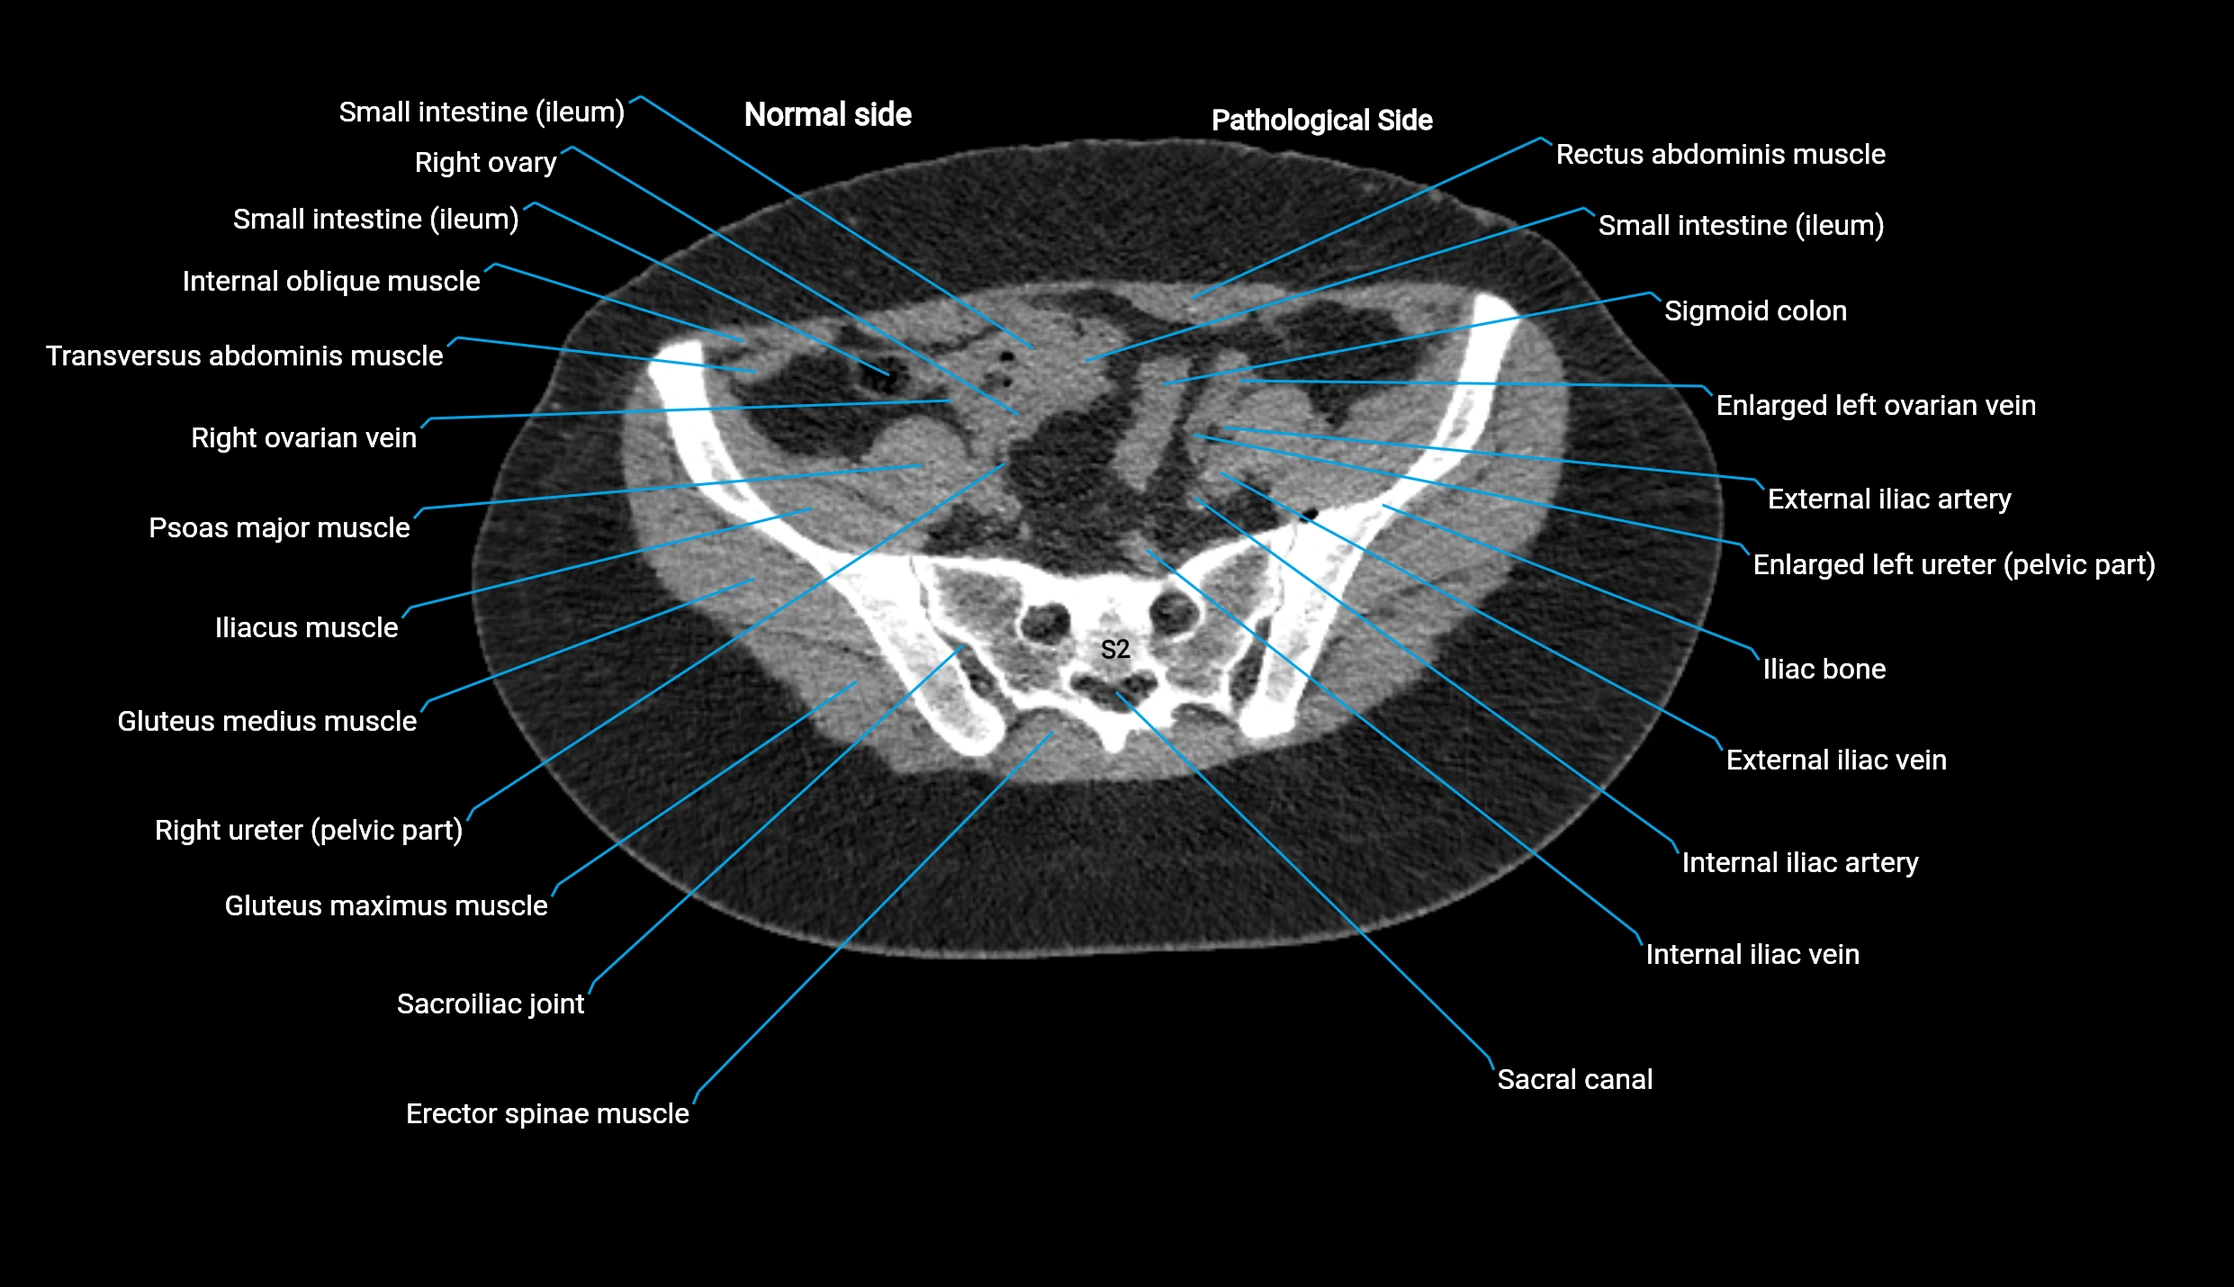

CT image

image